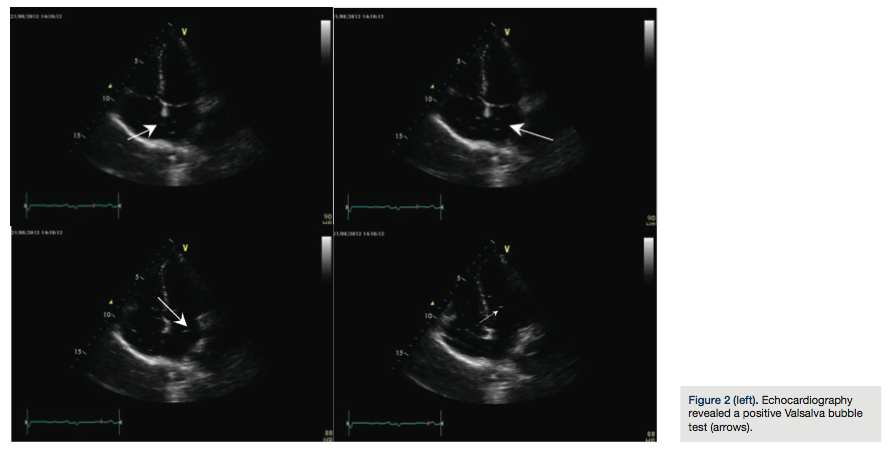

not show any anomalies, with the exception of recurrent typical migraine attacks with aura. Clinical examination showed that the young woman’s general physical condition was normal; resting ECG showed no irregularities. A two-dimensional color-flow echo Doppler scan of the neck vessels showed arteries free of atherosclerotic lesions. An echo Doppler study of the lower extremities was negative for thromboses. All laboratory test tests were normal. Transthoracic two-dimensional color Doppler echocardiography demostrated a patent foramen ovale and Chiari’s network; subsequent ecocontrast with agitated saline bubble contrast demostrated a right-to-left shunt of microbubbles at rest and following the Valsalva maneuver

(Figure 2). Transesophageal echocardiography confirmed a large PFO.

We report the case of a young woman who presented with cryptogenetic stroke. Transthoracic echcardiography revealed a residual PFO with a positive Valsalva bubble test. The patient underwent a percutaneus PFO closure with the Gore Septal Occluder. The procedure was performed under transesophageal echocardiography to guarantee proper sizing and position of the device. A number of devices are available for closure of PFOs. The Gore Septal Occluder consists of a frame of five nickel-titanium wires with a platinum core which is covered by a tube of expanded polytetrafluoroethylene film12 and is quickly endothelialized. The device is placed via standard femoral venous access. The benefits from its use seem to be easy and quick implantation, adaptability for a variety of atrial septal anomalies, and good tolerability without residual shunt.12 However, large-scale studies are needed to confirm the safety and efficacy of the device and especially to investigate possible late complications.